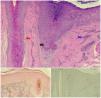

Dermoscopy revealed moderate perifollicular scaling and erythema, with isolated hairs. We performed 2 skin biopsies. Histopathology revealed damage to the basement layer of the hair follicles, with abundant necrotic keratinocytes, in association with lamellar fibrosis, fibrosis in the adjacent dermis, and an inflammatory mononuclear infiltrate in the follicular infundibulum. Staining with Fontana-Masson, S100, and Melan-A was negative for melanocytes (Fig. 3), thus confirming the diagnosis of FFA and vitiligo co-occurring in the same lesion. The Vitiligo Extent Score (VES) was 1.1031 and the Frontal Fibrosing Alopecia Severity Score (FFASS) was 11.6.

A, Histopathology revealed vacuolization of the basement layer, abundant necrotic keratinocytes (black arrow), dermal lamellar fibrosis (red arrow), and moderate inflammatory mononuclear cell infiltration (blue arrow). B, Fontana–Masson staining was negative for melanocytes. C, Melan-A immunohistochemical staining was negative for melanocytes.